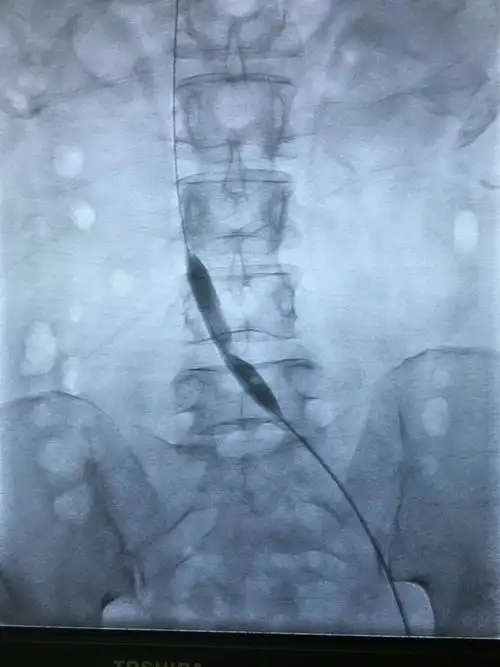

给予球囊扩张可见明显切迹